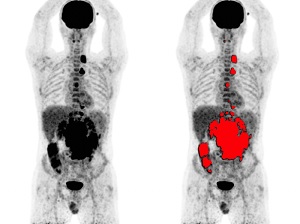

Un equipo de investigadores de la Universitat Politècnica de València (UPV), el Consejo Superior de Investigaciones Científicas (CSIC) y la Universitat de València (UV) participan en IMAS (Imagen Molecular de Alta Sensibilidad), un proyecto de investigación y desarrollo impulsado por la Conselleria de Sanitat Universal i Salut Pública de la Generalitat Valenciana con el objetivo de desarrollar un nuevo dispositivo de tomografía por emisión de positrones (PET) - prueba de medicina nuclear que se utiliza, por ejemplo, para la detección de cáncer, afecciones cardíacas o trastornos neurológico como el Alzheimer- que mejore las prestaciones de los equipos actuales gracias a avances a nivel de sensibilidad y resolución espacial.

El proyecto IMAS pretende dar un salto cualitativo en la sensibilidad de los escáneres PET al aumentar de manera significativa su extensión axial y abarcar el cuerpo completo del paciente. Ello se conseguirá manteniendo una excelente resolución espacial, lo que permitirá reducir la dosis de radiación al paciente que se le realiza la prueba diagnóstica.

Concretamente, IMAS aspira a mejorar la detección del par de fotones producidos por la aniquilación del positrón a través del aumento considerable de sensibilidad, optimizando la resolución espacial para observar con mucho mayor detalle las estructuras, y mejorando la resolución temporal para generar imágenes de mayor calidad. Además, una ventaja adicional de este equipo es que su extensión axial permitirá adquirir simultáneamente y analizar procesos dinámicos que tienen lugar en el cuerpo.

IMAS conseguirá mejorar la detección de las lesiones de menor tamaño, reducir el tiempo de exploración, aumentar el número de pacientes explorados por día, adaptar el diagnóstico al paciente pediátrico, permitir la realización de estudios dinámicos -visualizando, simultáneamente, procesos fisiológicos de regiones distantes del cuerpo- y, en definitiva, aumentar la calidad asistencial, con diagnósticos más precisos y cuantificables mediante la detección automática de los órganos y las lesiones combinada con la extracción de biomarcadores de imagen (textura, heterogeneidad, farmacocinética…) y sus cambios dinámicos temporales.